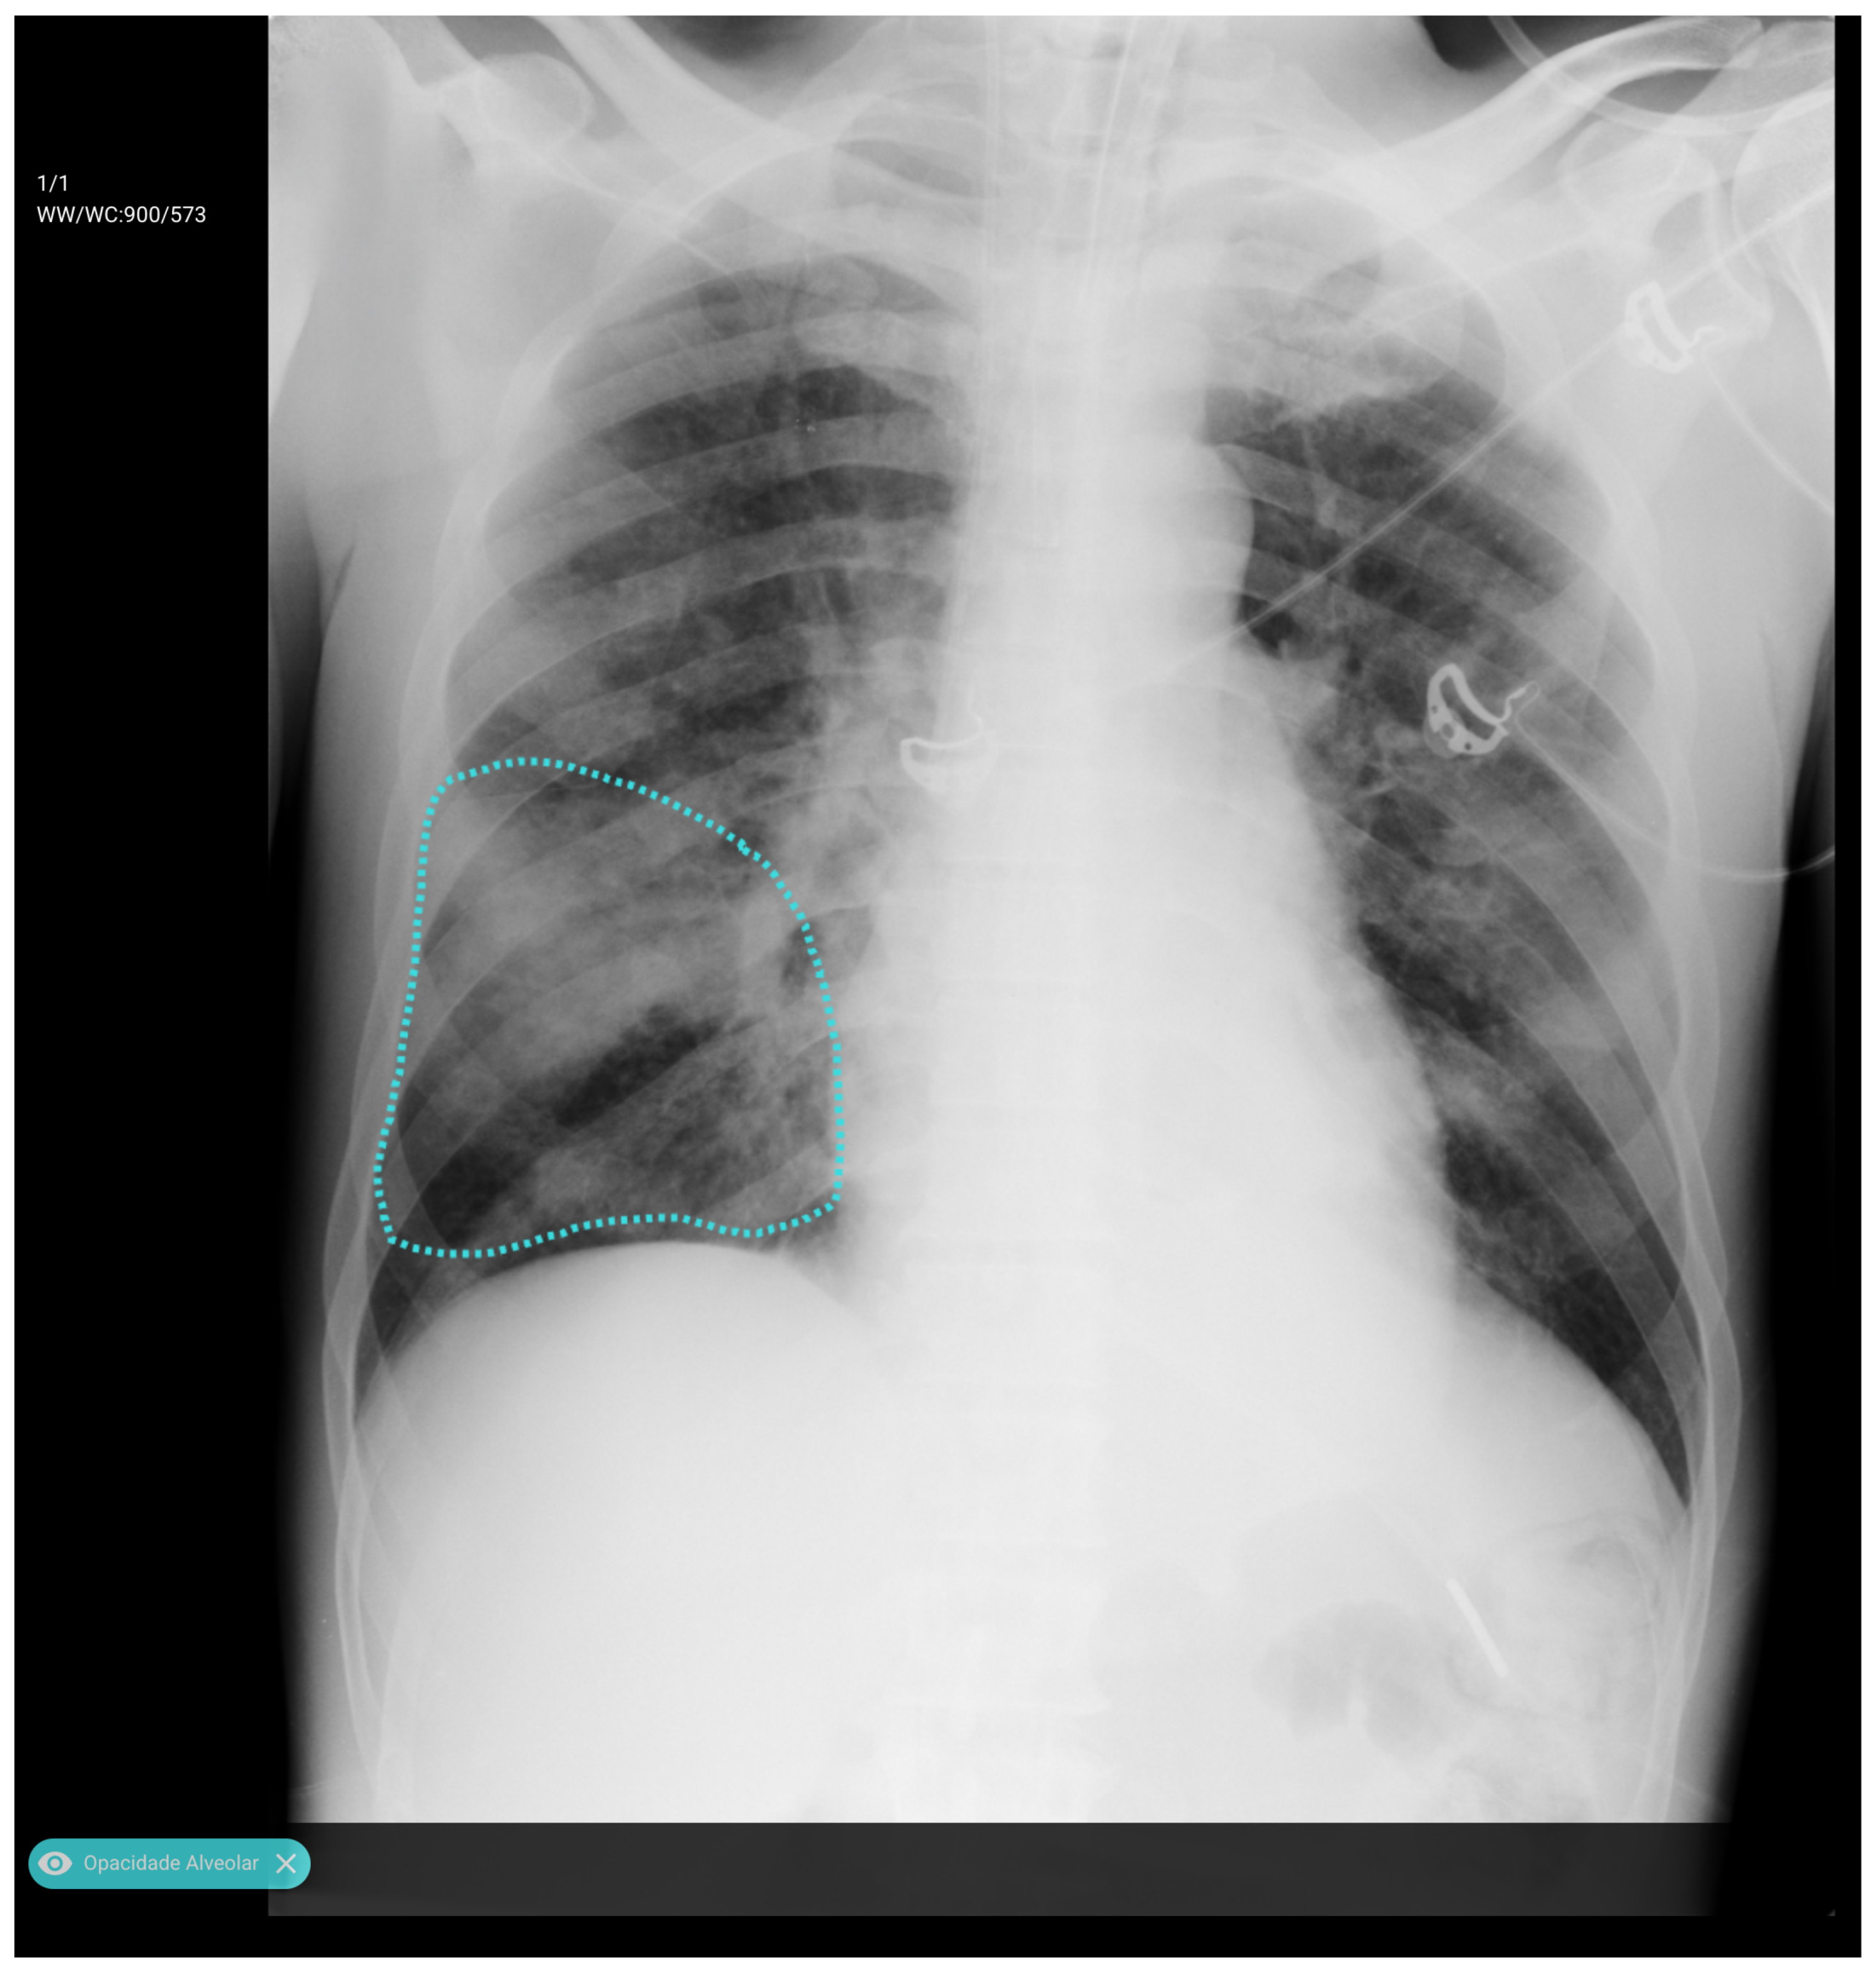

3.3. Error Analysis

An analysis of the algorithm’s false negatives revealed a nuanced performance profile, where a specific miss did not always equate to a complete system failure. Across the board, a substantial number of cases with a false negative for a particular pathology were nevertheless correctly identified as abnormal by the general “yes-finding” classifier or had other co-occurring true positive pathologies. For example, out of 38 false negatives for opacity, the algorithm correctly identified the exam as abnormal in 25 cases. In many instances of a missed finding, the algorithm successfully detected other pathologies within the same study. Misclassification was another notable source of error, where an existing pathology was detected but incorrectly labeled, such as opacities being predicted as masses or nodules (Figure 4). Radiologist review of these false-negative cases frequently noted findings that were “subtle,” “small,” “doubtful,” “seen on lateral image only,” or “non-specific.” In other cases, the algorithm correctly identified a more critical finding, like a large pleural effusion, while missing a secondary, less significant pathology (Figure 3). Figure 9, Figure 10 and Figure 11 illustrate false negative cases for opacity, pneumothorax, and nodule, respectively. This highlights the inherent limitations and inevitable failures of this kind of system.

Figure 5. A true positive example of opacity and consolidation (left) and its contour line generated image (right).